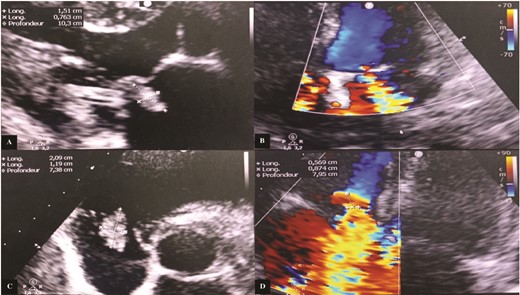

Transesophageal echocardiography (TEE) showed a mitral valve with vegetation prolapsing into the left atrium and a tricuspid valve with vegetation measuring 26 mm in its largest dimension, prolapsing into the right atrium (Fig. 2).

Transesophageal echocardiography images. (A) Incidence 113° showing vegetation attached to the free edge of the anterior tricuspid leaflet measuring 26.3 mm in long axis. (B) Surface area of the vegetation attached to the anterior tricuspid leaflet estimated at 2.51 cm2 and circumference of 8.06 cm. (C) Color Doppler showing significant mitral regurgitation. (D) Incidence 113° showing vegetation attached to the large mitral leaflet measuring 15 mm in long axis.